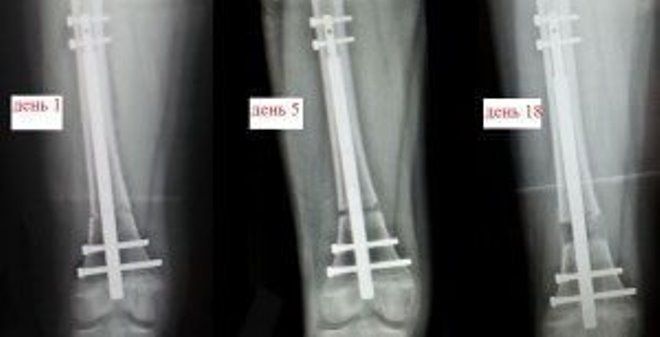

Удлинение ног аппаратом Илизарова

Одним из популярных методов увеличения длины ног, который используют ортопедические хирурги, является метод Илизарова. Эта операция считается одной из самых доступных и простых. Суть процедуры заключается в следующем: на коже пациента выполняются несколько надрезов, затем рассекается часть костной ткани, после чего устанавливается специальный аппарат для наружной фиксации. Он фиксируется с помощью спиц, которые проходят через кость, и постепенно растягивает ее. Крепления необходимо регулярно подтягивать, поэтому пациенту приходится проводить значительное время в стационаре под наблюдением медицинского персонала. Однако за одну процедуру можно увеличить рост на 6-8 см.